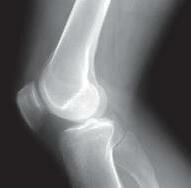

Bij een neutraal alignement (= recht been) gaat ongeveer 70% van de druk door het mediale compartiment en slechts 30% door het laterale. Bij een O-benen (varus) loopt dit vanaf 3-5° varus op tot 100% mediaal, bij X-benen is er meer druk lateraal (foto 1).

Foto 1 Alignement onderste lidmaat. Bij een neutraal of normaal alignement, wordt ongeveer 70% van het lichaams gewicht door het mediale compartiment gedragen. Bij varus (O-benen) is dit 100%. Bij valgus (X-benen) is de druk in het lateraal compartiment verhoogd.

Daarom zal artrose bij een patiënt met onderliggend een varusafwijking zich quasi altijd bevinden thv het mediale compartiment. Door de artrose, wordt de kraakbeenlaag dunner in het mediale compartiment, waardoor het been nog meer in varus kantelt en de druk op het mediaal compartiment zal verder verhogen. Daarom wordt dit ook een variserende gonartrose genoemd. Bij een valgus alignement zal de artrose het vaakst optreden in het lateraal compartiment met hierdoor een progressieve X-stand van het been. Dit wordt dan een valgiserende gonartrose genoemd.